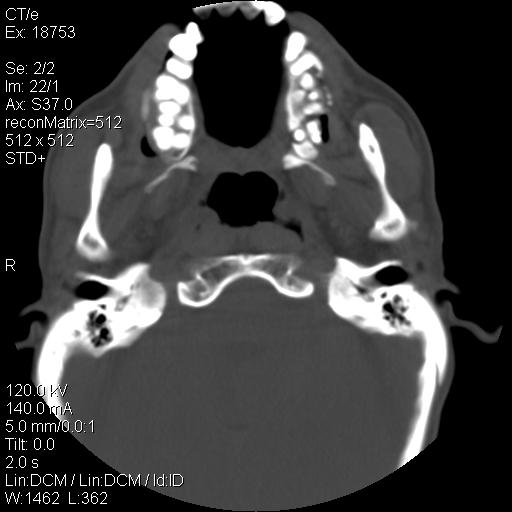

标题: CT21693:男 58岁 右侧咽部疼她2天余 PE:右侧扁桃体肿大 压痛 [打印本页]

标题: CT21693:男 58岁 右侧咽部疼她2天余 PE:右侧扁桃体肿大 压痛

考虑感染性病变可能性大,建议抗炎治疗后复查,必要时鼻咽腔镜活检排除占位。

结合病史,考虑感染性病变;建议抗炎治疗复查排除肿瘤性病变。

右化脓性扁桃体炎症伴咽后壁脓肿形成.